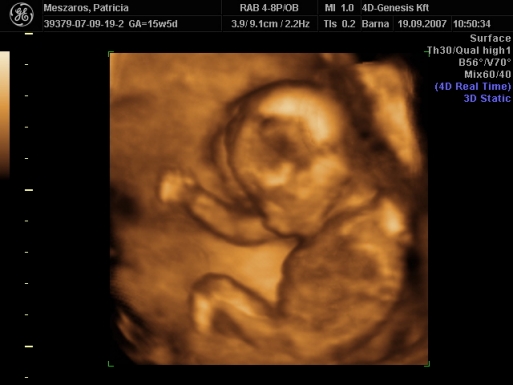

2007.09.19 19:15

2007.09.19 19:16